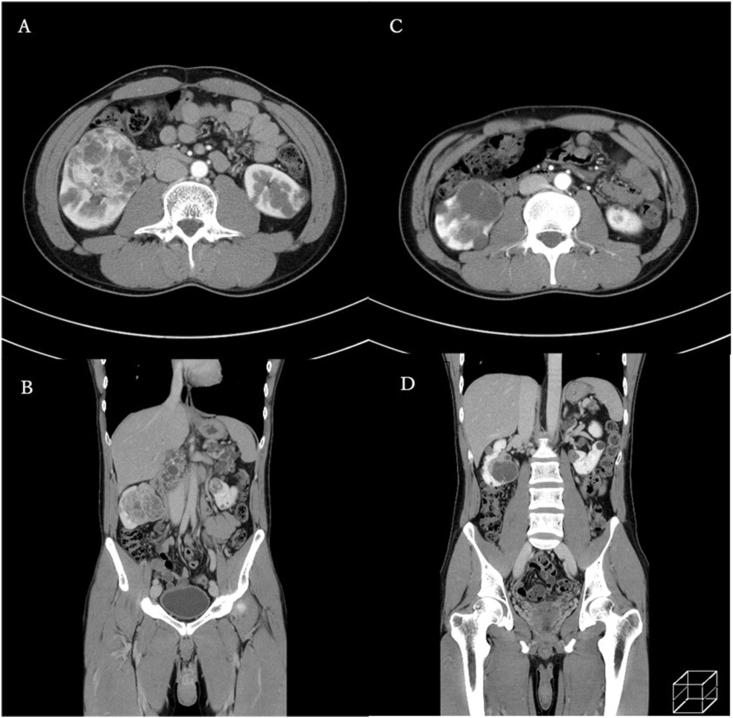

von Hippel-Lindau (VHL) disease is an autosomal dominant hereditary disease with benign and malignant tumors occurring in various organs including the kidneys. In patients with renal cell carcinoma (RCC) lesions in both kidneys, it is difficult to determine the treatment strategy. We report a case of VHL disease with RCC treated via partial nephrectomy after 6 months of axitinib therapy. Then, the patient continued to receive low-dose axitinib therapy without any signs of tumor progression for 3 years after surgery. Axitinib combined with surgery might be a treatment option for patients with VHL disease harboring bilateral RCC.

希佩尔-林道(VHL)病是一种常染色体显性遗传病,在包括肾脏在内的多个器官中会出现良性和恶性肿瘤。对于双侧肾脏均有肾细胞癌(RCC)病变的患者,很难确定治疗策略。我们报告了1例VHL病合并RCC的患者,在接受阿昔替尼治疗6个月后行部分肾切除术。术后,患者继续接受低剂量阿昔替尼治疗,术后3年无任何肿瘤进展迹象。阿昔替尼联合手术可能是治疗双侧RCC的VHL病患者的一种治疗选择。